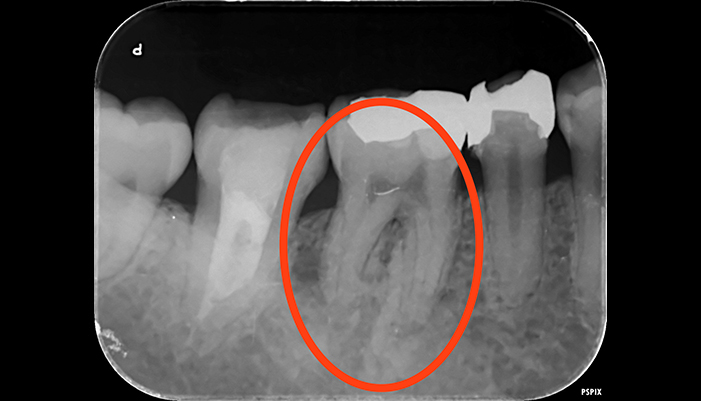

治療前

治療後

| 主訴 | 虫歯を治したい |

|---|---|

| 治療期間 | 1回 |

| 費用 | 再根管治療132,000円(税込)+ ファイバーコア44,000円(税込)= 176,000円(税込) |

| 治療内容 | ラバーダムを用いて無菌的な環境下で再治療(過去に根管治療をしている歯の治療)を行いました。 過去に詰めた修復物の周りが虫歯になってしまっていたため、マイクロスコープ下で虫歯を完全に取り切り、 NiTiファイルを用いた根管形成、薬液や超音波器具による洗浄、体に馴染みの良い材質による充填、被せ物を支え、再感染しないように土台を立てました。 |